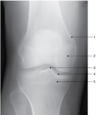

What is indicated by 1? A - Lateral condyle B - Lateral epicondyle C - Medial condyle D - Medial epicondyle

D - Medial epicondyle Figure 2-16 shows an AP projection of the knee. The distal femur and proximal tibia and fibula are seen. The femorotibial joint space is open, and the tibial articular facets of the tibial plateau (number 4) are demonstrated. The intercondylar eminence (number 3) is seen. Number 2 is the medial femoral condyle; number 1 is the medial femoral epicondyle; and number 5 is the medial tibial condyle.